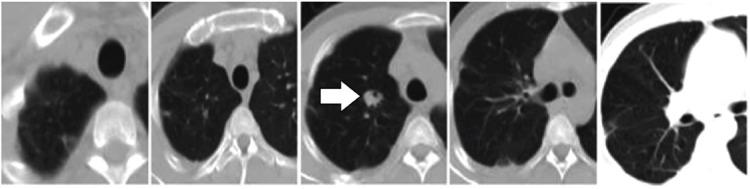

We present a case of primary pulmonary arterial sarcoma (PPAS) treated with endostatin (endostar) injection and radiotherapy  discuss the diagnosis, clinical manifestations, and pathology of PPAS. The patient complained of cough with sputum, fever, and chest pain with hemoptysis. Numerous nodules were observed in the computed tomography (CT) scan. The patient was diagnosed with pulmonary embolism (PE) by computed tomography pulmonary angiography (CTPA). The pathology and immunohistochemistry results indicated soft tissue sarcomas, indicative of angiosarcoma. The nodules shrunk after 5 courses of endostatin and one course of radiotherapy, as determined in the CT scan. Primary pulmonary arterial sarcoma is clinically rare with nonspecific symptoms. Hence, it can be easily misdiagnosed as PE, and biopsy must be performed for confirmation. Current treatment methods, including surgery, are limited. Therefore, administration of endostatin injection combined with other therapies may be an alternative treatment methods.

我们报告了一例原发性肺动脉肉瘤(PPAS)患者,该患者接受了恩度(恩替佐滨)注射液和放疗治疗。我们讨论了 PPAS 的诊断、临床表现和病理学。患者主诉咳嗽、咳痰、发热和咯血胸痛。胸部计算机断层扫描(CT)显示多发结节。计算机断层肺动脉造影(CTPA)诊断为肺栓塞(PE)。病理和免疫组织化学结果显示软组织肉瘤,提示为血管肉瘤。CT 扫描显示,患者在接受 5 个疗程的恩度和 1 个疗程的放疗后,结节缩小。原发性肺动脉肉瘤临床罕见,症状无特异性。因此,它很容易被误诊为 PE,必须进行活检以明确诊断。目前的治疗方法包括手术,但均有限。因此,注射用恩度联合其他疗法可能是一种替代治疗方法。